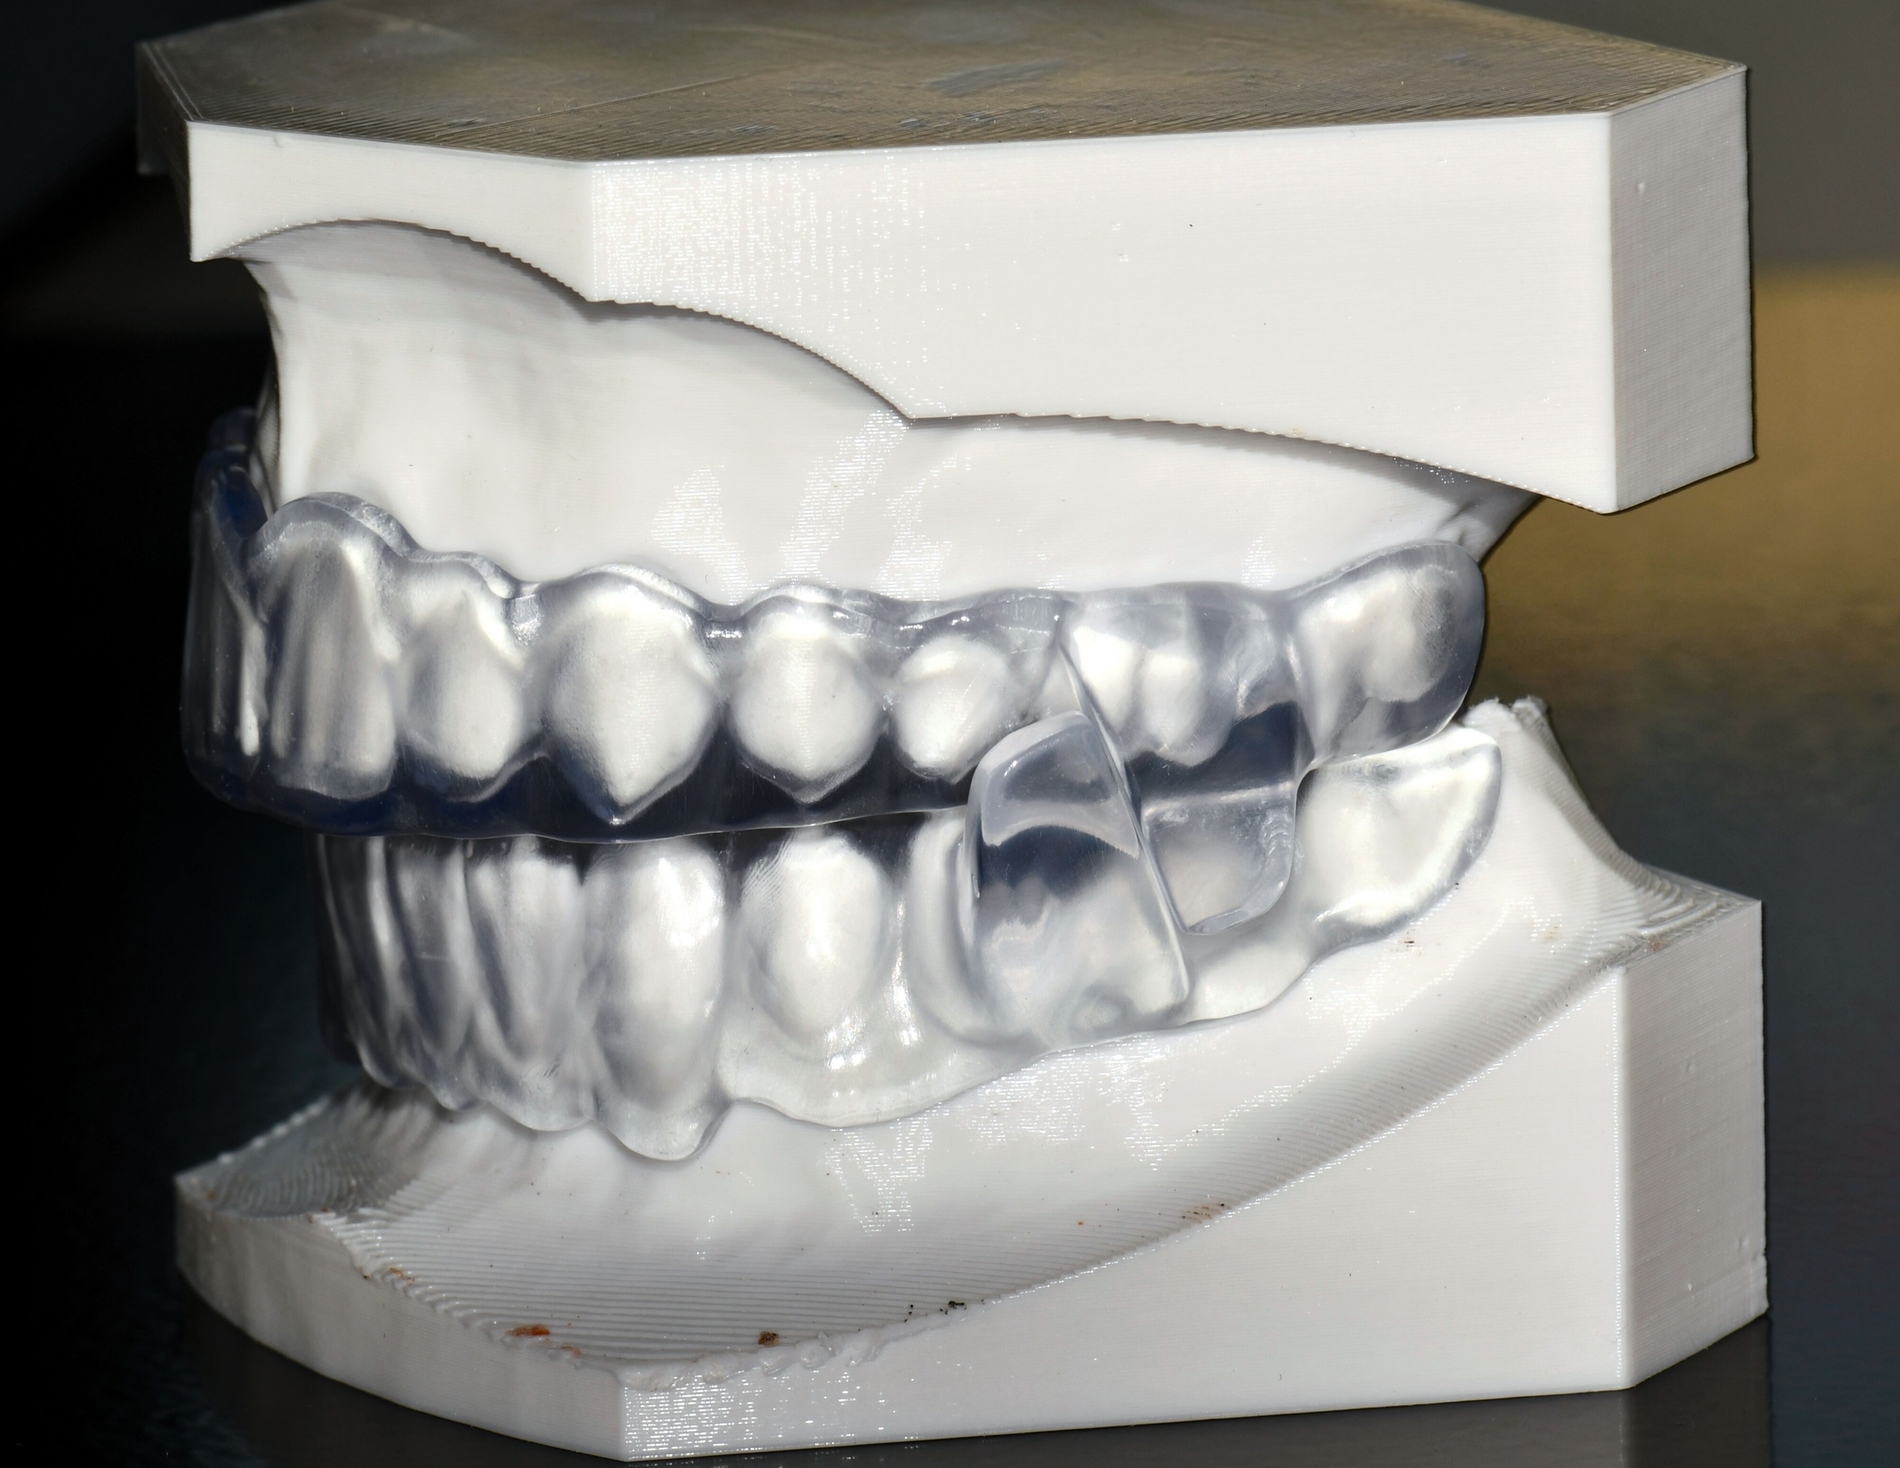

Aligner

Unter den digital gefertigten kieferorthopädischen Apparaturen sind Aligner wohl das bekannteste Beispiel [Ercoli et al., 2014, Robertson et al., 2020]. Die Herstellung von Alignern selbst basiert(e) jedoch auf einer manuellen Fertigung anhand 3-D-gedruckter Modelle und stellt(e) somit bisher eher eine partiell automatisierte Fertigung dar. Die neuesten Entwicklungen erlauben mittlerweile eine Fertigung im direkten 3-D-Druckverfahren [Tartaglia et al., 2021], so dass mühsame, zeitaufwendige Zwischenschritte der manuellen Fertigung entfallen (Abbildung 1a). Weiter profitieren die Patienten von individuelleren Fertigungsmöglichkeiten, da durch die Umsetzung im 3-D-Druck zusätzliche Elemente einfacher und stabiler in den Aligner inkorporiert werden können (Abbildung 1b).